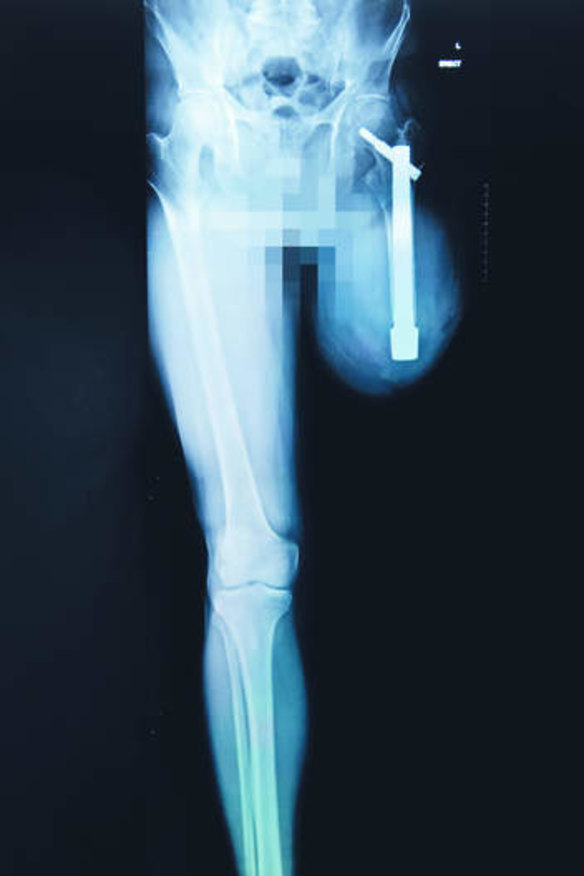

For one, he can now feel the difference between surfaces - concrete, grass, carpet - when he walks on his artificial leg, which is connected to a titanium rod inserted directly into the femur.

Osseointegration helps above-the-knee amputees. The titanium rod is inserted in the bone and connected through an opening or stoma in the stump to an external prosthetic limb.